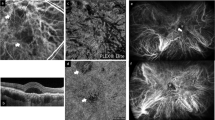

Choroidal phenotype in patients with pachychoroid-associated central serous chorioretinopathy (CSCR)

In a normal choroid, large vessel diameters are highly variable. Despite being large and protruding anteriorly, the overlying choriocapillaris remains visible as a thin hyporeflective layer in SD-OCT (Fig. 7a). In eyes with pachychoroid-associated diseases, vascular dilation can be extremely important, leading to choriocapillary compression, and extending up to Bruch’s membrane, in areas where the choriocapillaris cannot be distinguished and the overlying RPE forms bumps, displacing the outer retinal bands (Fig. 7b, arrows). On top of this typical sign, the vessels are surrounded by irregularly shaped hyperreflective structures with blisters, distinct from hyperreflective dots as they do not vary with time or with activity of the disease. Such irregular perivascular hyperreflectivity is very characteristic of this pathology, as previously described [24], and is present in patients whose RPE cells and outer retina are still maintained, as shown in Fig. 7B of this middle-aged men who presented with resolving CSCR in his left eye. In more advanced and complex CSCR [21], atrophy of the RPE and the outer retina allows a more direct visualisation on the choroid, with increased light passing through. An example of such patient is shown in Fig. 8, where RPE atrophy is highlighted by the extensive window defect shown in the early-phase fluorescein angiography (Fig. 8a), the highly visible vessels on early-phase indocyanine green (ICG) angiography (Fig. 8c) and on B-scan SD-OCT with photoreceptor disorganisation and RPE loss (Fig. 8e). On the infrared image, large choroidal vessels appear dark, surrounded by a white filamentous network particularly dense around vessels (Fig. 8b). Superposition on infrared image with ICG angiography clearly shows that the hyperreflective network does not correspond to vessels but surround and / or cover them (Fig. 8b). On SD-OCT B-scan (Fig. 8e, f), the exact location of one hyperreflective filamentous structure corresponds to a perivascular elongated and individualised band. Comparison with the histological organisation of the ChNS highly suggests that those hyperreflective structures, visible on infrared imaging and SD-OCT correspond to pathological nerves, similar to the irregular and dilated nerves imaged in P1.hMR using electron microscopy. The size of the nerves observed in humans as compared to choroidal vessels is compatible with the size of images observed on clinical images.

Foveal SD-OCT in healthy and CSCR conditions. a Foveal SD-OCT of a healthy retina, showing a thickened choroid with dilated choroidal vessels. In the enlarged quadrant, vessels are visualised as round hyporeflective structures with a homogenous hyperreflective border, more pronounced towards the RPE. The choriocapillaris remains visible despite choroidal enlargement. b In this chronic resolving CSCR, pachychoroid is observed, as reported on SD-OCT of the left eye. An enlarged choroidal vessel in the perifoveal zone is visualised underneath the RPE and prevents correct visualisation of the choriocapillaris (white arrows), associated with discrete RPE elevation and outer retina displacement. In the enlarged quadrant, several hyperreflective dots are observed, both surrounding large choroidal vessels and within the choriocapillary space, with a granular irregular appearance

Clinical features on multimodal imaging of a 55-year-old man with chronic CSCR and widespread pigment epitheliopathy. The RPE atrophy is highlighted by the extensive window defect shown on early-phase fluorescein angiography (a), which allowed a more detailed visualisation of choroidal vasculature in the early-phase IGC cliché at 1 min (b), showing the dye in the intravascular space. On infrared en-face imaging (c), choroidal vessels were visualised as dark areas (yellow star). Adjacent to choroidal vasculature dark reflectance, white linear structures with increased IR reflectance were observed (blue arrowhead). These were hypofluorescent on ICG (b, corresponding yellow stars and arrowheads). d SD-OCT EDI scan showing photoreceptor disorganisation and RPE loss, pachychoroid and enlarged choroidal vessels. The green vertical line shows that the B-scan is placed over the white linear structure in the en-face IR image (e, white arrow). The corresponding location on SD-OCT (f, enlarged image) shows a hyperreflective area (yellow circle) very close to enlarged choroidal vessels (white star), underneath the choriocapillaris

Potential application for clinical images analysis

In patients with pachychoroid and central serous choroidopathy, typical perivascular densities and hyperreflective structures have been recognised [24], but until now they have not been connected to neural structures. Hyperreflective dots have been identified as potential inflammatory cells, but such dots vary with time and activity of the disease [52], which is very different from the perivascular hyperreflective bands that remain stable over time. Whilst the present work better characterised the ChNS using either histology or immunohistochemistry, recognised its density around vessels, its organisation, the large size of certain fibres, the presence of ganglion cells and its proximity with the choriocapillaris, it seems very plausible that the ChNS could be imaged by SD-OCT or infrared images when the RPE is damaged. In case of choroidal neuropathy, the morphological changes of nerves, shown in the P1.hMR mouse model, could translate to the abnormal perivascular structures observed in CSCR cases. Interestingly, genetic variants in VIP receptor 2 (VIPR2), have been associated with choroidal thickness and with pachychoroid-associated CSCR [40], reinforcing the idea of a potential causal link between neural pathology and pachychoroid. The association of this choroidal phenotype with evidence of systemic dysautonomia reinforces the hypothesis that the pachychoroid may result from a choroidal neuropathy.

In summary, we have described the distribution of ChNS and its close anatomical relationship with all choroidal vessels, immune cells and RPE in the human and rodent choroid, suggesting a central role of ChNS not only in the regulation of choroidal blood flow, but also in the function of the innate immune system and of the RPE. The abnormal diameter of choroidal vessels and RPE changes observed in P1.hMR mice could be a consequence of MR-induced deregulation of the ChNS. The morphological changes in the choroidal nerves observed in P1.hMR mice could be translated to the abnormal hyperreflective perivascular structures present on OCT and ICG of patients with pachychoroid spectrum diseases. The hypothesis that MR-mediated choroidal neuropathy could be the link between corticoids and pachychoroid, and the use of imaging markers of choroidal neuropathy in the diagnosis and treatment of choroidal diseases merits further clinical investigations.